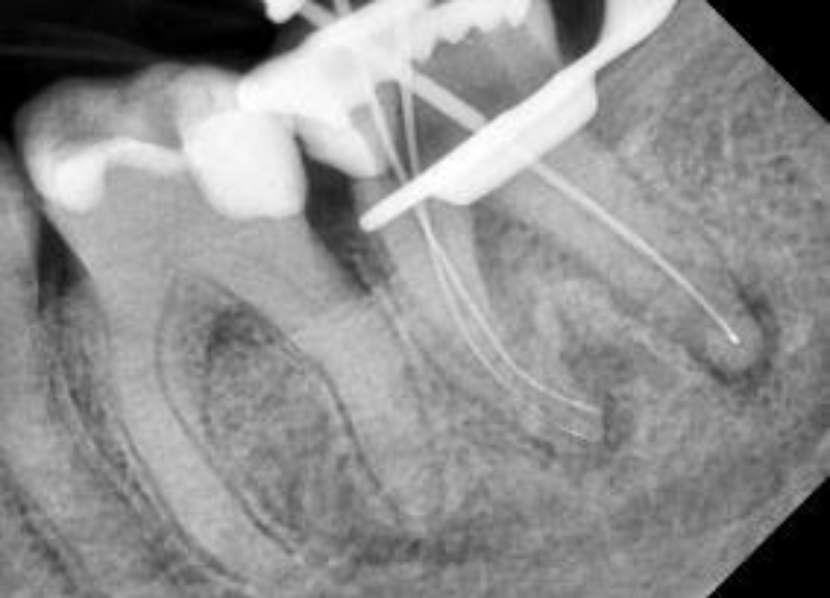

Wenn man sich dieses präoperative Röntgenbild ansieht, sind zwei Hinweise zu diesem endodontischen Fall zu erkennen (Abb. 1): Obliteration der Pulpakammer und enge Kanäle Ungewöhnliche Anatomie der distalen Wurzel

Mit hochtourigen Diamantbohrern wurde eine konventionelle Zugangskavität angelegt und die drei Öffnungen wurden mit Ultraschallspitzen lokalisiert. Die KFeile #08 wurde verwendet, um das endodontische System aller Wurzeln zu erkunden, wobei aber der Apex im distalen Kanal nicht erreicht werden konnte. Das Aufweiten und die Instrumentierung im mittleren Drittel erfolgten mit einer reziprok arbeitenden kleinen (gelben) EdgeOne-Feile (Edge Endo, Albuquerque, NM), die mit Einwärts-Auswärts-Bewegungen von 1-2 mm im Wechsel mit bürstenden Bewegungen zum koronalen Erweitern der Kanäle verwendet wurde. Es wurde eine regelmäßige und reichliche manuelle Spülung mit Lösungen von 5% Natriumhypochlorit durchgeführt. Nach der Aufbereitung des koronalen und mittleren Teils wurde die Arbeitslänge mit der K-Feile #10 bestimmt und das Aufbereitungsverfahren mit martensitischen X7-Instrumenten (Edge Endo, Albuquerque, NM) in den Größen 17 und 25, Konizität .04 abgeschlossen. Die Instrumente wurden mit reziproker Rotation im Uhrzeigersinn (150°-30°) verwendet, um die Torsions- und Biegebelastung zu verringern (Abb. 2).

FALLBERICHT: Abb.1 Abb.2